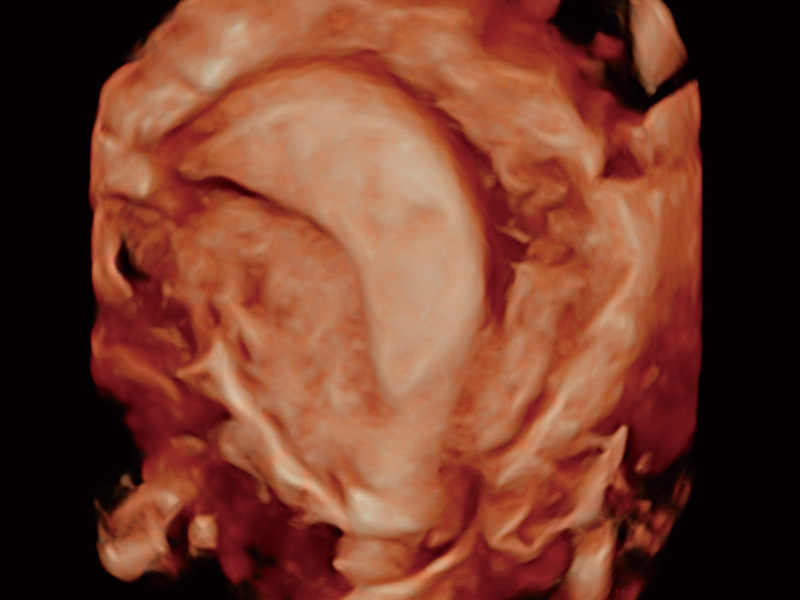

腔内容积探头

腔内三维成像技术获得显著提升,超大扇角在满足日常基础扫查的同时,支持卵泡自动测量及多种三维渲染模式,为您提供更多的诊断信息,尤其是在子宫畸形的诊断,内膜及肿瘤占位观测中起到了重要的作用。

子宫内膜息肉

输卵管间质部妊娠